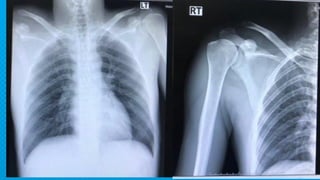

Film Rt. Shoulder transcapular

Film Rt. Shoulder AP

0.23 cm

0.69 cm

200 %Rt. Cc

distance more

than Lt

× Rt. AC joint injury gr,V

14 0.23 cm 0.69 cm 200%Rt. Cc distance more than Lt